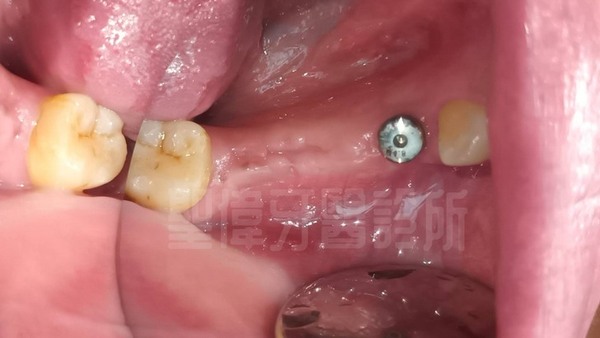

植牙後的狀況↑